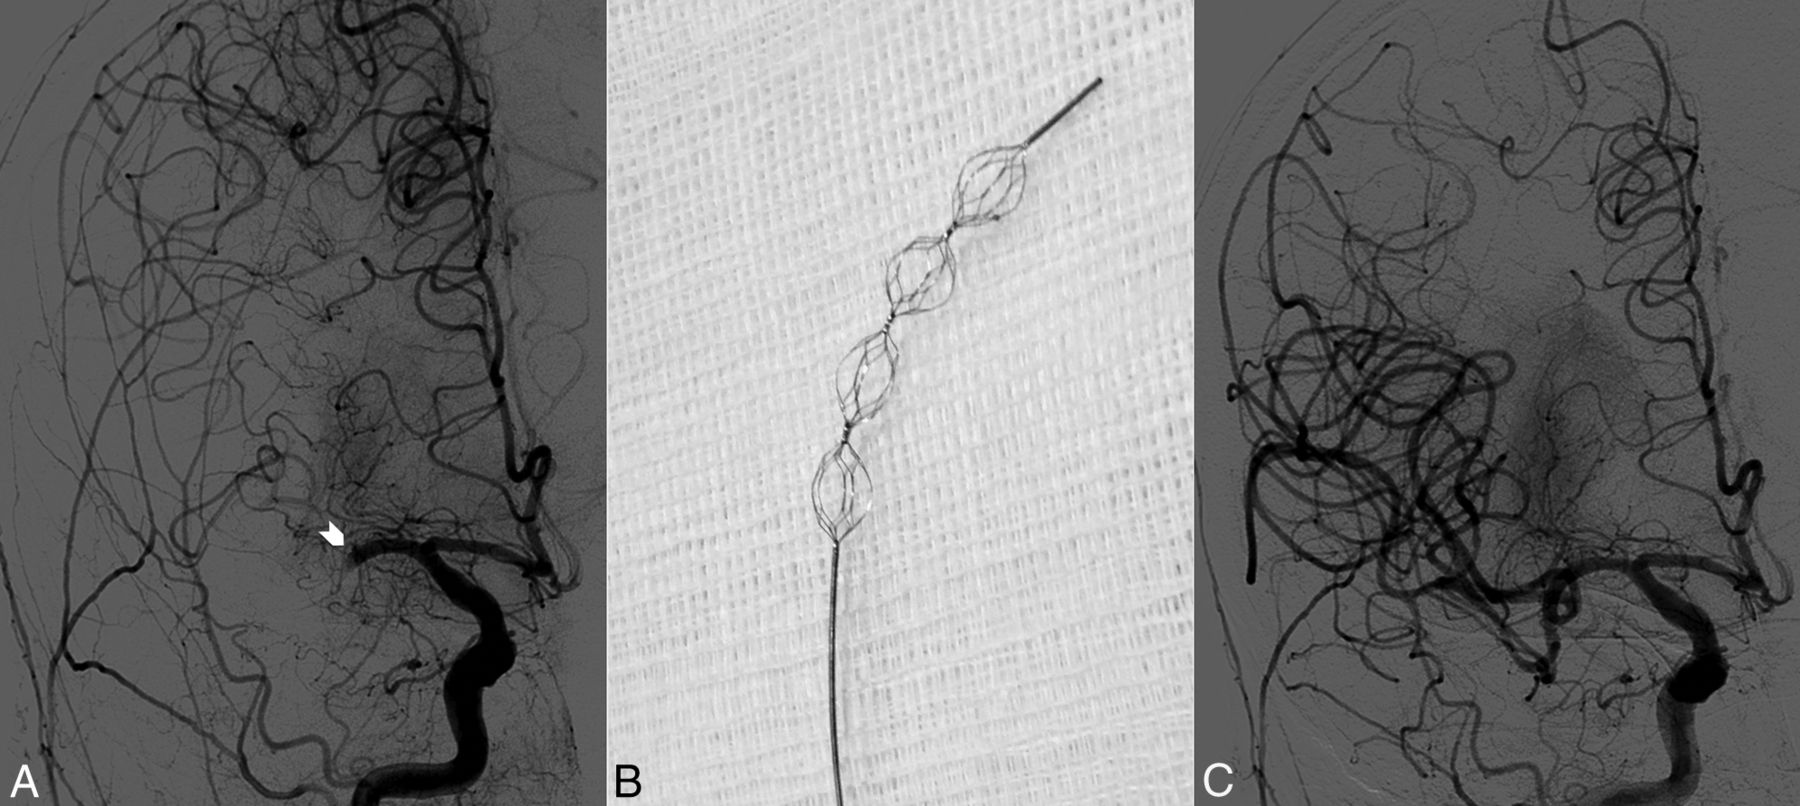

However, even the latest devices need to be deployed for several minutes before retrieving the thrombus and thus require precious time. Moreover, 1 device does not fit all occlusion types, and alternative effective devices are warranted. In this pilot study, we sought to determine the feasibility, efficacy, and safety of mechanical thrombectomy in patients with acute ischemic stroke by using the new Embolus Retriever with Interlinked Cages (ERIC; MicroVention, Tustin, California) (Fig 1B).

A, MCA M1 occlusion (white arrowhead). B, ERIC retriever tip. C, MCA M1 recanalized.

The new ERIC is formed by 3–5 interlinked cages with diameters ranging from 3 to 6 mm and a resulting working length of 15–44 mm (Fig 1). Thus, the number of working cages can be adjusted to the required working length. The ERIC is designed to retract the clot coaxially and prevent the captured clot from shearing off during retraction. All procedures were performed on an Allura Xper FD20/20 biplane angiography system (Philips Healthcare, Best, the Netherlands) according to the departmental protocol with intraprocedural modification if required. Briefly, an 8F balloon-guide catheter was placed in the distal common carotid artery. A heparinized saline solution was continuously perfused through the catheter during the procedure. With the balloon of the guide catheter deflated, a 0.0014-inch guidewire was advanced coaxially over a Headway 17 Advanced Microcatheter (MicroVention) within the occluded intracranial vessel and navigated distal to the clot. The Headway 17 microcatheter was then advanced over the wire through the clot and the guidewire was exchanged for the embolectomy device. The ERIC was advanced and deployed a few millimeters distal to the clot. The balloon of the guide catheter was inflated, and the microcatheter and the embolectomy device were gently withdrawn under continuous proximal aspiration with a syringe. A control angiography was performed to confirm recanalization and reperfusion. Modifications of the standard procedure are reported in On-line Table 1.